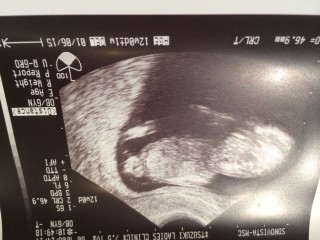

妊娠9週から 絨毛膜下血腫で出血。自宅安静。 12週に 診察して血腫がなくなったと 診断していただいたときのエコーです! 赤ちゃん元気に 大きくなってました!

5.6cmで162bpm(毎分の心拍)♡♡♡ エコー中ぐるっと回ったり、指をしゃぶるかのように口元に手をもっていったりしている様子を見ることが出来ました。まだ空腹感から吐き気を感じたり胃液を吐くほどですが赤ちゃんにも頑張って生まれてきてほしいですし、早く抱きしめてあげたいのでポジティブに頑張れます(*^^*)